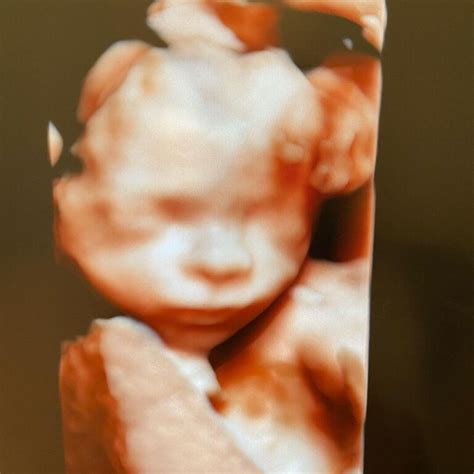

Morfologia fetală din trimestrul 3 de sarcină va dezvălui trasăturile fine ale micuțului. Ecografia din această fază poate fi utilizată pentru a evalua creșterea și dimensiunea fătului, pentru a examina localizarea placentei și cantitatea de lichid amniotic. Monitorizarea fătului (cardiotocografie - CTG) este utilizată pentru a înregistra ritmul cardiac fetal în raport cu contracțiile uterine.